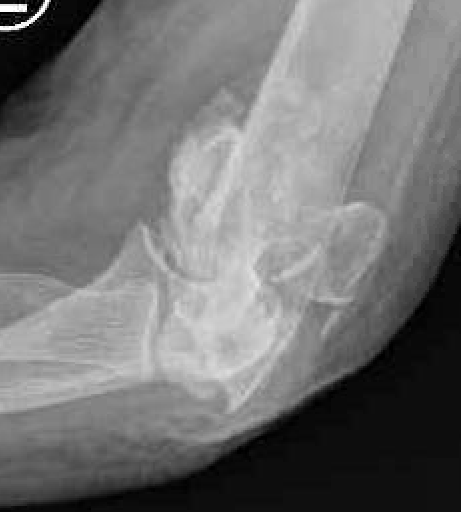

OTA / AO Classification

Type A: Extra-articular fracture

Type B: Partial articular fractures

Lateral condyle Medial condyle

Type C: Complete articular fractures